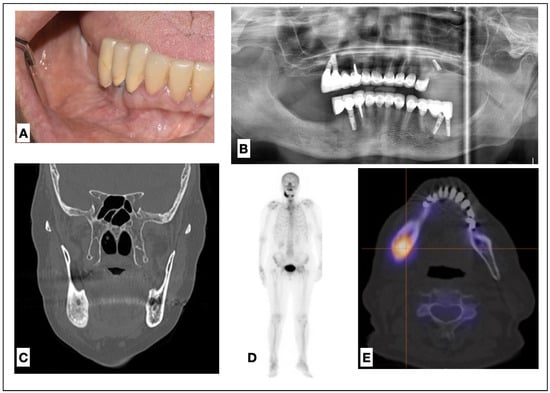

2.1. Patient 1